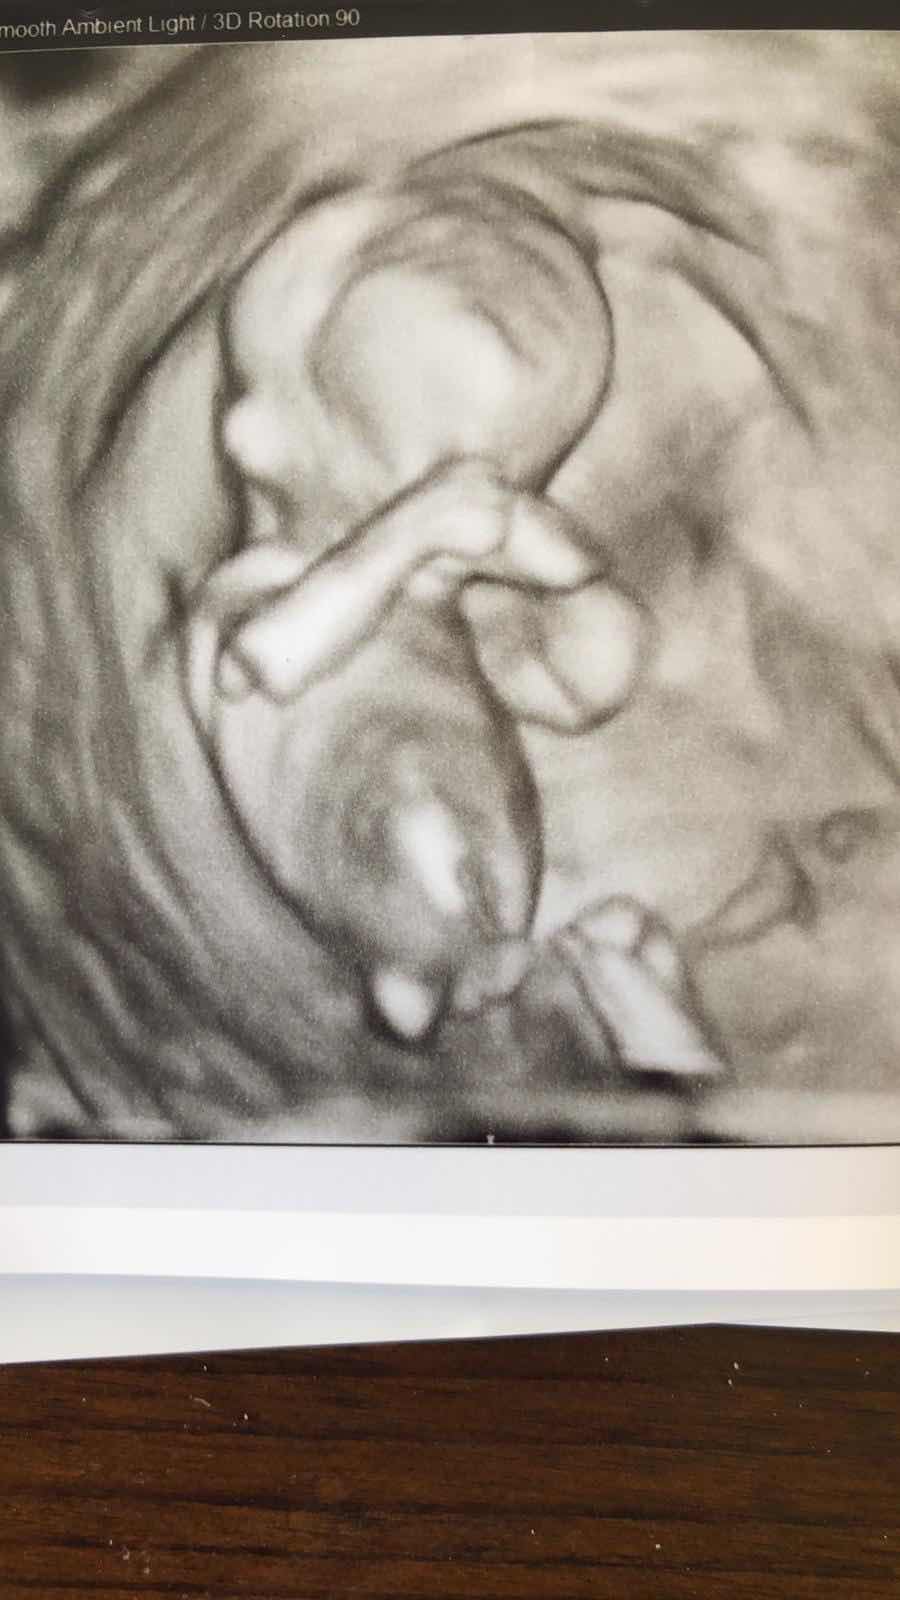

| Oi mãe! |

Mais uma vez escutei o coração do nosso baby. O vi se mexer ( para caramba). E ela analisou todas as medidas e tudo que era possível com 13 semanas de gravidez. Ao final, minha sogra retornou e conversou com a médica. A médica não falava inglês direito e eu lá com meu finlandês fajuto.

Havíamos feito os testes para saber as chances do nosso bebe ter alguma trissomia (13,18 ou 21), síndromes de Patau, Edwards ou Down. As chances eram baixas. Ela nos informou que o bebê estava “5 dias atrasado” nas escalas de peso/tamanho quando comparado à data prevista de concepção. ( no Brasil, a sonografista havia nos informado 2 dias). Também comentou que isso era normal e que eu poderia ter ovulado mais tarde, e que poderíamos rever tudo no próximo ultrassom.

O coração e sua formação pareciam dentro dos conformes, mas por precaução todos as próximas consultas seriam com ela, que era uma médica especializada em cardiopatias.